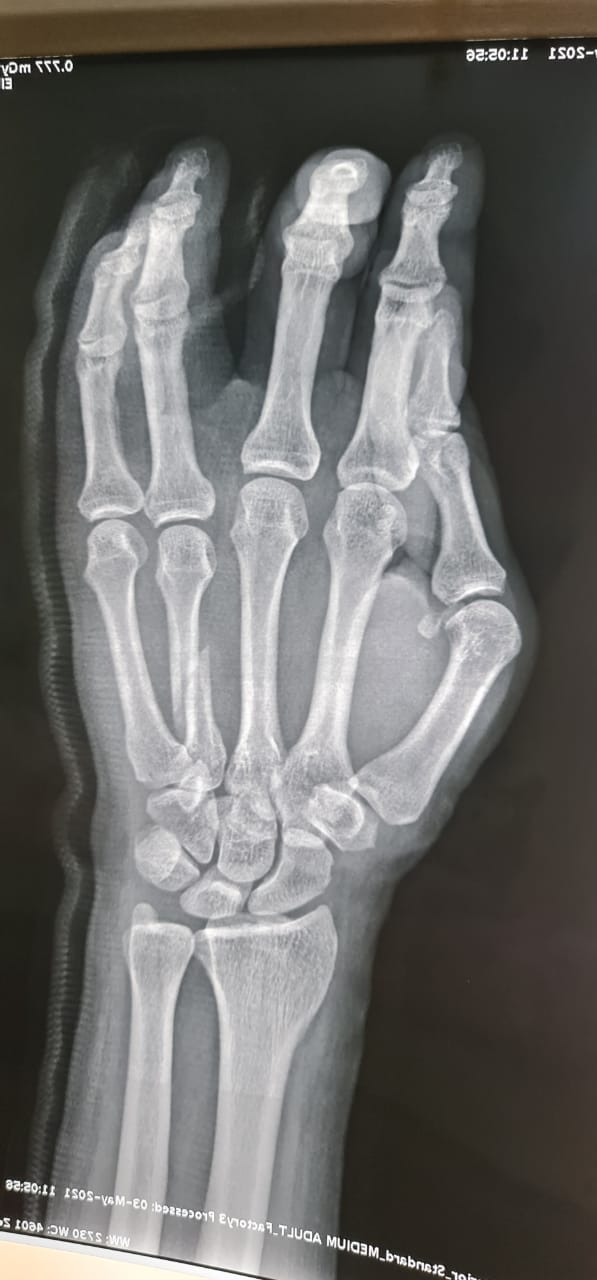

تمكّن فريق طبي متخصص بمستشفى حريملاء العام من إجراء تدخل عاجل و طارئ ، للتعامل مع حالة لمواطن سعودي خمسيني مصاب بكسر متزحزح بالمشطية الرابعة لليد اليمنى إثر حادث سقوط.

واستقبل قسم الطوارئ بالمستشفى المصاب حيث تم على الفور تشكيل فريق طبي مكون من أخصائيين قسم جراحة العظام والكسور بالمستشفى ، وقام الأطباء على الفور بعمل الإسعافات الأولية وإعطائه المحاليل والمسكنات والمضادات الحيوية، وتم عمل الأشعات العادية والمقطعية، التي أظهرت أن المريض يعاني من كسر متزحزح بالمشطية الرابعة لليد اليمنى ويحتاج تصليح مفتوح للكسر وتثبيت بشريحة ومسامير ذات طابع خاص، فتم نقل المريض إلى غرفة العمليات وإجراء عملية تثبيت بشرائح ومسامير.